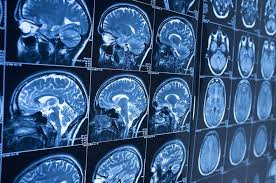

images